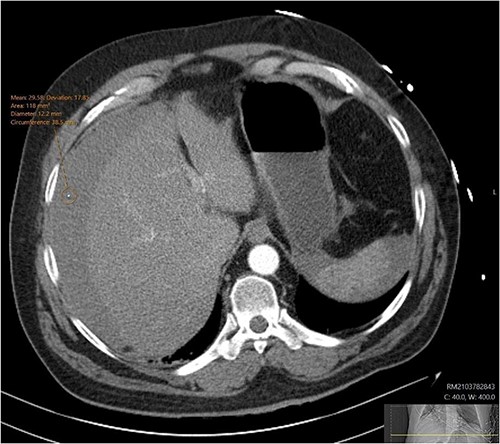

During admission the patient’s abdominal pain gradually improved, his Hb increased and he had no further coughing episodes. The patient was therefore stepped down to oral antibiotics and considered safe for discharge. A CT-AP four weeks post-discharge demonstrated a persisting 60 x 40 mm liquefying haematoma in the small bowel (Fig. 4), resolution of the peri-hepatic haematoma (Fig. 5) and interval reduction of the peri-splenic and pelvic haematomas. Given these improvements and the patient’s lack of significant symptoms, a plan to actively survey his progress was made.

Follow up CT angiogram showing improvement in perihepatic haematoma. Figure 5 is another axial section from the patient’s CT angiogram performed 4 weeks following discharge and shows resolution of the perihepatic haematoma seen previously. Together with the other sections of the CT angiogram and the patient’s overall clinical state, the image represents a significant improvement in the patient’s intra-abdominal bleeding.